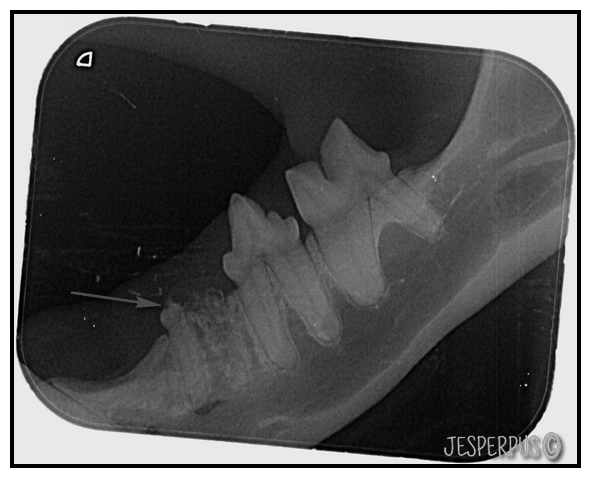

Her er tennene mine før behandlingen.

Blå pilen viser at det begynner å bli en rosa strek i tannkjøttet langs tannen. Irritasjon

Rød pil viser opphopning av plakk. I grunn ikke noe veldig alvorlig.